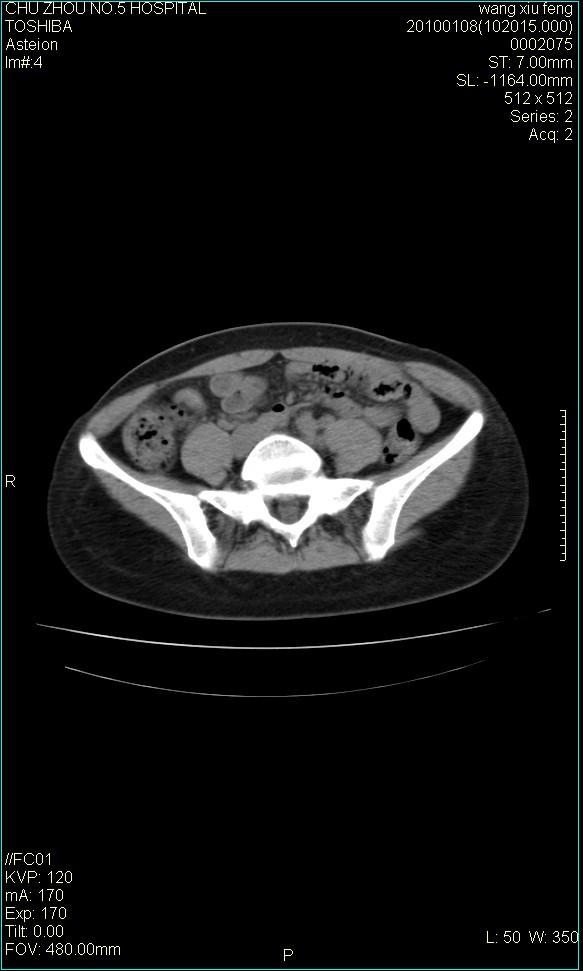

标题: CT24042:子宫右上方囊性包块,性质???? [打印本页]

标题: CT24042:子宫右上方囊性包块,性质????

f-41,左乳腺ca术后4年,b超示:子宫右上方囊性包块约5.5*3.4cm,前日行胸部ct平扫未见明显异常。